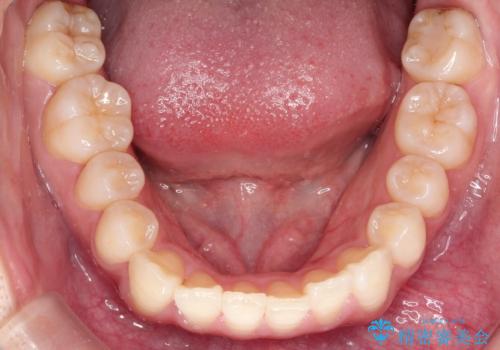

前歯の叢生・Ⅱ級咬合を改善|TADを用いた遠心移動+インビザライン矯正

- 前歯のガタガタと臼歯関係のⅡ級(上顎の歯列が前方にある状態)を改善するため、TAD(歯科矯正用アンカースクリュー)を使用したインビザライン矯正を計画しました。まずTADを上顎の適切な位置に設置し、それを固定源にして奥歯を後方(遠心)へ移動させ、十分なスペースを確保します。その後、インビザラインによるマウスピース矯正で前歯の歯列を整え、臼歯関係を正常化します。治療期間はおよそ1年半〜2年を想定しています。

前歯部の叢生(ガタガタ)と臼歯関係のズレを改善するため、抜歯をせずに奥歯を後方へ移動(遠心移動)させることを選択しました。TADという小型のアンカースクリューを顎骨に設置することで、確実かつ効率的に奥歯を後方へ移動させました。併せて透明で目立ちにくいインビザラインを用いることで、審美性を保ちながら治療を進めることが可能でした。患者様の負担が少ないマウスピース矯正と固定源のTADを組み合わせることで、抜歯することなく歯並びと噛み合わせを大幅に改善でき、大変ご満足いただけました。